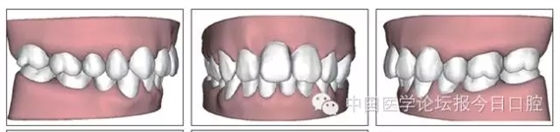

本病例為慢性牙周炎致前牙漂移、深覆(牙合)患者。本病例采用無托槽隱形矯治技術(shù)進行治療。無托槽隱形矯治器具有可摘戴、便于口腔衛(wèi)生維護和牙周治療的優(yōu)點,更適合于伴有牙周炎的錯(牙合)畸形患者的治療。 患者男,48歲,前牙有縫、前突求診。 患者面部對稱,側(cè)面觀上頜前突,下頜后縮。 口內(nèi)情況:恒牙列,24、34、44缺失,磨牙Ⅲ類關(guān)系,上牙列散隙,上前牙扇形漂移。前牙深覆(牙合)、深覆蓋??谇恍l(wèi)生較差,11與12間牙齦乳頭紅腫,多個牙探診有牙周袋形成,11松動Ⅰ度,余切牙松動(-),患者面像及口內(nèi)像如圖1、2所示。 圖1 治療前面像 圖2 治療前口內(nèi)像 全口曲面體層片(圖3)顯示,患者全牙列牙槽骨吸收;根尖片(圖4)示11近中牙槽骨角形吸收已達根尖1/3,21牙槽骨嵴頂吸收至根1/2,23牙槽骨近中骨板角形吸收至根1/2。磨牙區(qū)骨嵴頂吸收3mm。治療前頭顱側(cè)位片見圖3,治療前ODS模型見圖5。 圖4 治療前根尖片 圖5 治療前ODS模型 牙型:安氏Ⅲ類。骨型:Ⅱ類。面型:上頜前突,下頜后縮。 問題列表為:①上牙列間隙;②上切牙病理性牙移位;③前牙深覆(牙合)、深覆蓋;④24、34、44缺失;⑤慢性牙周炎。 矯治目標包括:①排齊牙列,關(guān)閉牙列間隙;②改善前牙深覆(牙合)、深覆蓋;③改善牙周狀況。 矯治設(shè)計有:①牙周基礎(chǔ)治療與維護。②壓低、內(nèi)收上切牙,關(guān)閉上牙列間隙。③壓低下切牙,伸長下后牙,整平Spee曲線,改善前牙覆(牙合)、覆蓋。 患者進行全口齦上潔治、齦下刮治,口腔衛(wèi)生宣教,并按牙周醫(yī)師的要求,每2~3個月行牙周檢查與治療。 牙周基礎(chǔ)治療結(jié)束3個月,開始隱形矯治。于14、25、35、36、45、46上粘接附件(圖6),于16、26(牙合)面粘接(牙合)墊。 圖6 ODS設(shè)計附件粘接圖示 矯治過程中注意(牙合)墊是否脫落或磨損,及時修補。 注意上前牙內(nèi)收時有無咬合干擾,及時調(diào)(牙合)。下頜前磨牙伸長到位后,磨除16、26(牙合)墊。 下頜佩戴第24步矯治器時,分別在36、37、46、47的頰、舌側(cè)粘接舌扣,矯治器上預(yù)留伸長空間,用3/16英寸、3.5盎司皮圈牽引,輔助伸長下磨牙(圖7)。 患者共戴用矯治器上頜32步,下頜26步。 矯治后,牙列間隙關(guān)閉,面型及覆(牙合)覆蓋改善。11根尖片(圖8)顯示,治療后較治療前,牙周支持組織增加,牙槽骨角形吸收區(qū)水平向縮小0.3mm,垂直向縮小0.6mm。11松動Ⅰ度,余切牙無松動。 圖8 治療后根尖片 圖9 治療后口內(nèi)像 圖10 治療后X線檢查 圖11 治療后ODS模型 正畸-牙周聯(lián)合治療對于牙周組織的影響 多學(xué)科綜合治療牙周炎患者不再是正畸治療的禁忌證。良好的牙周治療為正畸治療中的牙齒移動打下堅實基礎(chǔ),而正畸治療排齊牙齒、去除(牙合)干擾,有利于牙周健康。 牙周炎患者的正畸治療必須在牙周炎癥得到控制后才能進行,否則,菌斑會隨著牙齒的移動,特別是壓低而使牙周炎癥加重。牙周炎的正確診斷、牙周炎癥控制、正畸治療中和治療后的認真維護是治療成功的關(guān)鍵。根據(jù)臨床需要,一般每2~4周做一次潔治,每3個月進行牙周評估,同時患者必須進行非常良好的日??谇恍l(wèi)生維護。 固定矯治器使得牙周檢查、潔治和日??谇恍l(wèi)生維護變得困難,隱形矯治器可自行摘戴,便于患者日常維護和牙周治療,節(jié)約時間,提高菌斑控制效果。 有臨床研究表明,對于存在(牙合)創(chuàng)傷,伴有角形吸收的患牙,經(jīng)過牙周翻瓣手術(shù)控制住牙周炎癥后,使用正畸輕力壓低患牙,可以改善牙槽骨吸收的程度,并獲得一定程度的牙周新附著。本病例切牙壓低后,原來的牙槽骨吸收有改善。 病理性牙移位 病理性牙移位(PTM)在重度牙周炎患者中的發(fā)生率為30%~50%,且常見于上前牙區(qū)。其主要由于牙周支持組織喪失尤其是骨組織的丟失,咬合因素(如后牙缺失、前牙深覆牙合、牙合創(chuàng)傷等),頰舌唇肌力量不平衡及牙周和根尖周組織炎癥所致,是牙周炎患者要求正畸治療的主要原因之一。 PTM須通過正畸、牙周聯(lián)合,有時須配合修復(fù)才能達到理想的治療效果。正畸治療通常是壓低牙齒,臨床研究表明,牙周手術(shù)配合正畸壓低可以產(chǎn)生新附著,有利于PTM牙周組織的恢復(fù)。 本病例右上中切牙牙槽骨角形吸收,在盡量保證治療前后根尖片投照角度一致的情況下,以鄰牙作為校準,在根尖片上對治療前后的骨量進行評價,治療后牙槽骨角形吸收區(qū)水平向縮小0.3 mm,垂直向縮小0.6mm。盡管根尖片并不能說明骨量改變,但從影像學(xué)上能看到骨吸收區(qū)域有所減小。 無托槽隱形矯治器矯治牙周病的優(yōu)勢 無托槽隱形矯治器具有可摘戴、便于口腔衛(wèi)生維護和牙周治療的優(yōu)點,更適合于伴有牙周炎的錯(牙合)患者的治療;同時,無托槽隱形矯治器佩戴后具有牙弓夾板和(牙合)板的作用,可有效減少側(cè)向力,有利于牙周的恢復(fù)和減輕牙齒松動;由于無托槽隱形矯治器的設(shè)計是在三維數(shù)字模型上進行的,每個矯治器移動牙齒的數(shù)量和每個牙齒的移動距離可以得到量化控制,因而可以根據(jù)患者牙槽骨水平和對矯治力的耐受情況個性化設(shè)計矯治力,并且可以根據(jù)矯治中牙齒移動情況調(diào)整后續(xù)矯治器的設(shè)計。 有關(guān)磨牙伸長 單純使用無托槽隱形矯治器同步伸長后牙比較困難。該病例先使用磨牙(牙合)墊打開咬合,通過矯治器伸長前磨牙,在前磨牙建立咬合后,磨除磨牙上的(牙合)墊,通過輔助牽引伸長磨牙,最終達到伸長后牙、整平Spee曲線的目的。 史真,主任醫(yī)師,現(xiàn)任北京黃寺整形外科醫(yī)院口腔科主任,第四軍醫(yī)大學(xué)口腔正畸學(xué)碩士,為世界正畸醫(yī)師聯(lián)盟(WFO)會員、全軍口腔醫(yī)學(xué)專業(yè)委員會委員、中華口腔正畸專業(yè)委員會委員、中華醫(yī)學(xué)美學(xué)與美容學(xué)會齒科美容學(xué)組成員、北京口腔醫(yī)學(xué)會兒童口腔專業(yè)委員會常務(wù)委員、北京口腔醫(yī)學(xué)會正畸專業(yè)委員會委員、《中華醫(yī)學(xué)美學(xué)與美容》雜志審稿專家,是我國最早開展無托槽隱形矯治技術(shù)的口腔醫(yī)師之一。